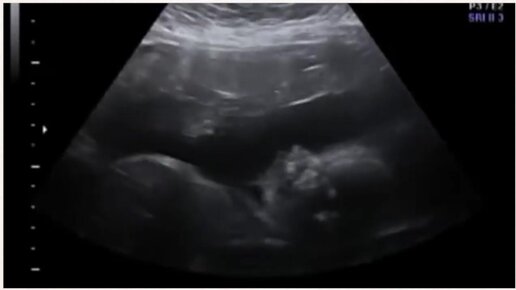

УЗИ на 26 неделе беременности